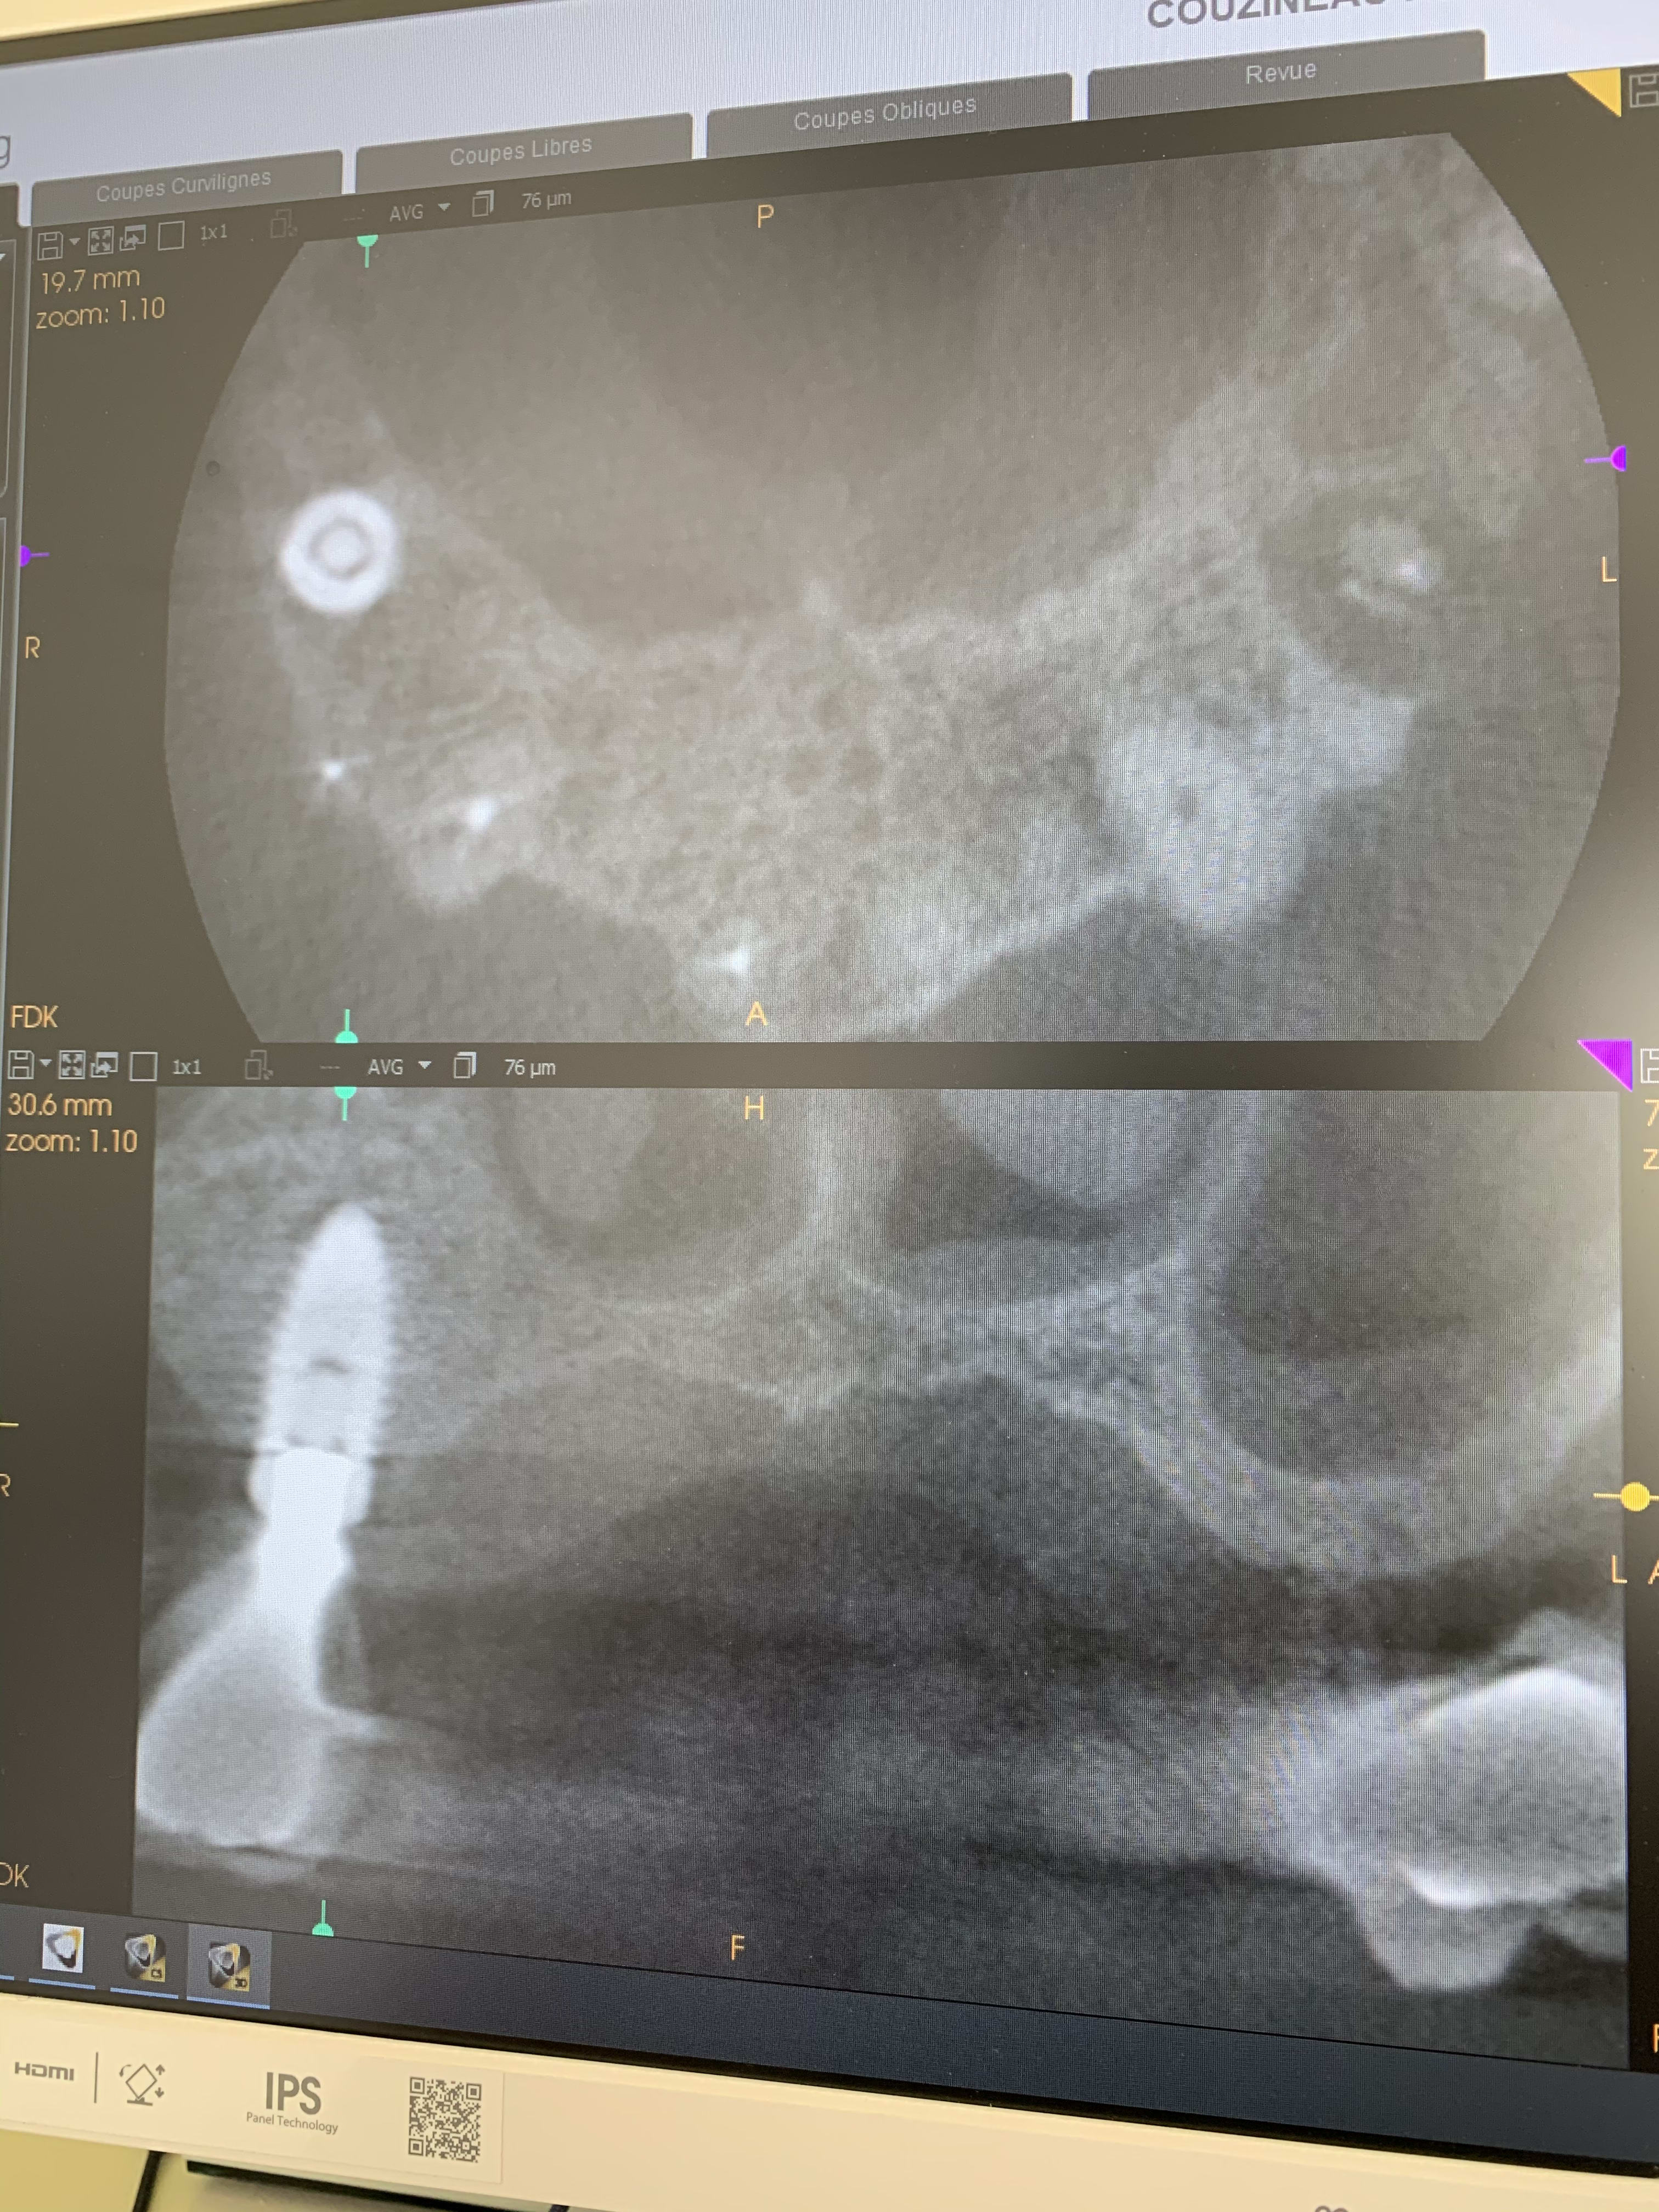

Il y a vraiment des différences de dingue entre les machines !

Les images 3 et 4, les images 6 et 7 sont prises à quelques années d’intervalles.

La machine de 2008 fait très peu d’artefacts, celle de 2018 énormément. Elle à le mar pour les « supprimer », mais ça n’arrange rien !

Les artefacts métalliques sont bien différents selon les machines.

A l’adf on me dit « regardez on voit même les spires des implants », avec ma bécanne de 2008 je vois les spires des vis dans les implants, les têtes de vis... je n’ai rien vu d’équivalent sur les machines récentes.

Les photos ne sont pas de très bonnes qualités, prises avec un 6S sans trop d’effort.

Regardez comme les tenons sont bien trop larges à la radio !

Les implants sont de gros pâtés blancs...